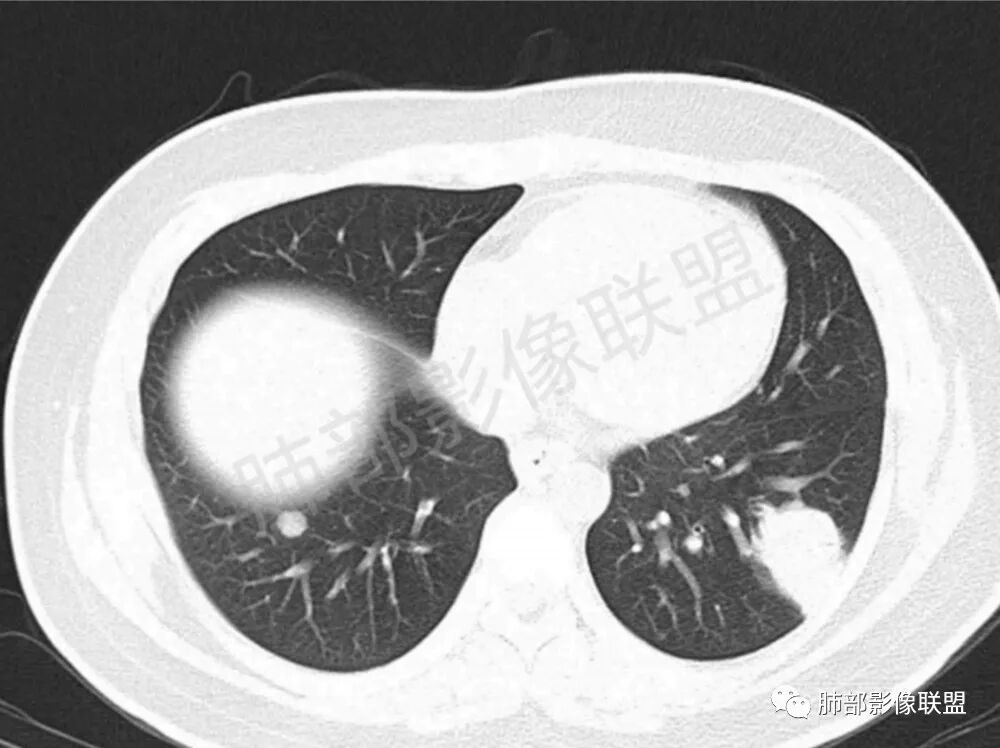

男性,22岁,HIV病史,症状半年,双肺多发大小不等结节影,边缘光滑,密度均匀,以胸膜下分布为主,部分与胸膜相连,胸膜下脂肪间隙可见,病灶近段支气管走行病灶内,远端似有堵塞,无增强图像,考虑隐球菌,鉴别:淋巴瘤,GPA

双肺多发结节影,膨隆,边缘光滑,圆顿,沿支气管血管束分布为主,部分贴胸膜,部分见空洞,空气支气管征

两肺多发结节性,大部分位于胸膜下,部分结节周围可见晕征。局部结节内可见扩张的支气管,纵隔淋巴结大,脾大,22岁男,HIV阳性,常规先考虑隐球菌。鉴别淋巴瘤,结核,马儿。

男,22,半年前咳嗽伴少痰,查HIV阳性,痰查TB阳性,既往有肺部斑片影伴空洞、纵隔淋巴结肿大、脾大。SCC、CA50、CA199、FER增高,此次胸部CT:两肺多发结节影,部分沿血管束分布,部分贴胸膜下,大小不一,密度不一,部分较散、边缘模糊,部分较实、圆钝、周围模糊晕,部分结节有支气管进入穿行自然,部分结节有血管分支自如通过。考虑HI∨相关淋巴增殖类病变,淋巴瘤?LYG?鉴别PC、TB。

青年男性,半年前咳嗽,HIV阳性,结核DNA阳性,肿标糖类抗原和铁蛋白增高。外院影像有纵隔淋巴结增大伴脾大,肺部病灶空洞。现在影像:肺内多发沿支气管分布(有支气管充气征,长轴沿支气管分布)及胸膜下分布(平行于胸膜)的大小不等结节,个别伴有空洞,双侧腋窝淋巴结肿大。纵隔图片不够,是否还有淋巴结肿大未知,脾脏未显示。

1.双肺多发大小不一结节,外围为主,边界尚清,部分周围似有GGO

2.类圆形,部分与胸膜相连,糊墙

3.支气管通畅或近端堵塞

影像学缺乏特征性,以支气管血管周围、胸膜下及双肺下叶周边多发结节影最多见,结节易坏死形成空洞,伴有游走性和多变性的特征,结节周围可有磨玻璃样晕征,有时也可见单发结节影、薄壁的囊状阴影或弥漫性浸润影。肺门、纵隔淋巴结肿大少见, 可见胸腔积液和气胸。

结节型∶表现为两肺多发大小不等的结节,以两肺中下野多见,结节边缘欠锐利;